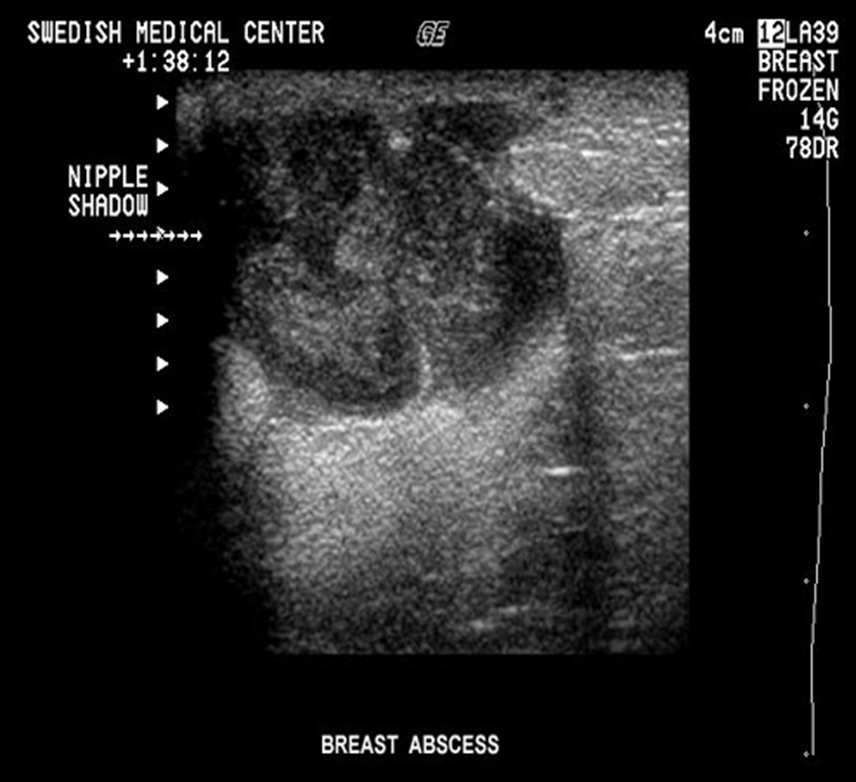

What is this image showing?

a breast abscess

What is the sonographic appearance of an abscess?

-diffuse mottled appearance

-irregular margins

-posterior enhancement

-low level internal echoes

-skin thickening

-hyperemia